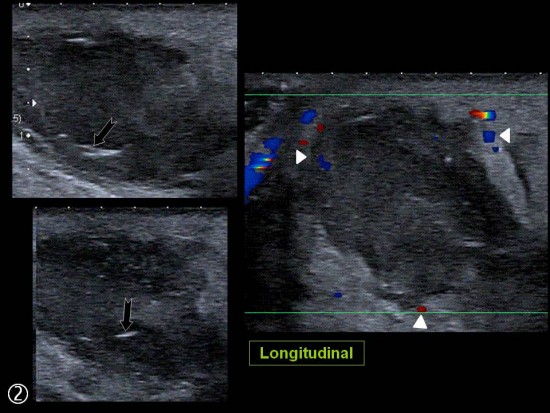

Patient de 44 ans presentant une masse peu sensible de la face palmaire du poignet avec des.

Une anomalie des membres caracterisee par labsence congenitale dun membre a partir du coude. Tumeurs pseudo tumeurs thrombose veineuse ulnaire du poignet irm.